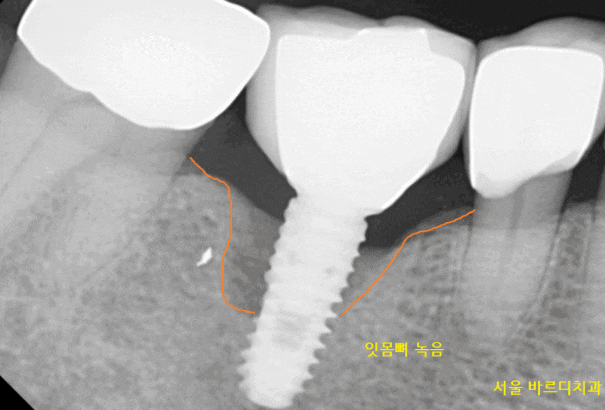

2020.11.04일 환자분께서

오른쪽 아래 잇몸이 불편하다고 내원해주셨어요.

자세히 살펴보니 임플란트를 했던 곳이

말썽이네요~

201104

예전에 다른 병원에서 임플란트를

수술받으셨다는데

하신지 오래되고 관리가 잘 안되다 보니

문제가 생겼습니다.

임플란트 주변 염증으로 인하여

잇몸 뼈가 녹아있었습니다.